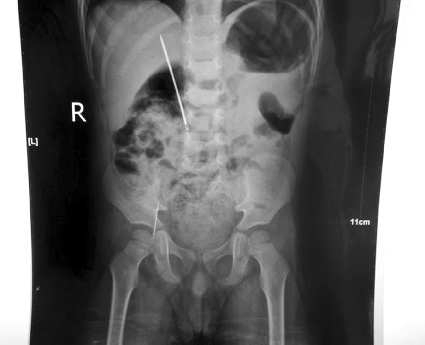

▲X线片显示小威右下腹腔内有两枚缝衣针。

为确定针的具体位置,保证缝衣针在孩子体内不游动,临沂市人民医院儿外一科专家急诊复查B超,B超显示孩子肝内有异物存在,X线片显示其右下腹腔内有两根缝衣针。因缝衣针在腹腔内存留时间太长,且已造成肠穿孔,肠蠕动恢复极慢。临沂市人民医院儿外一科医护人员考虑到如果不能保证手术将针全部取出,万一针刺入动脉,有可能造成大出血,所以手术前在患儿的手术方案上,除了技术方面的精心安排外,还千方百计地想着为其节省费用。

3月20日晚上8点,医院专家在全麻下为小威做了缝衣针取出手术,术中见右下腹回盲部有一长约3cm的钢针刺入后腹壁,右上腹见一长约7cm钢针经十二指肠向外上方刺入,两枚钢针已生锈,均被完整取出,同进时行十二指肠修补术。经过不间断的积极救治,小威终于转危为安。3月27日,小威康复出院。